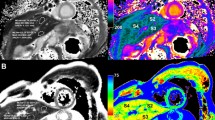

All T1 relaxation time calculations were performed in nordicICE (NordicNeuroLab, Bergen, Norway). Elliptical ROIs were placed in the portal vein in the raw images. The average signal from three ROI placements was used as input to the curve fit function in nordicICE to obtain \( \widehat{{T_{{1{\text{s}}}} }} \) for each scan. Figure 2 shows an example raw image with an ROI placed in the portal vein. When performing ROI placement as much as possible of the vein was included in the ROI, while visual artefacts and vessel wall were avoided.

Although not addressed directly in this study, there are some limitations when using a high flip angle for LL imaging. While this gave a significant reduction in \( \overline{{CoV_{\text{s}} }} \) in our study, it must be stressed that the high flip angle will result in increased saturation of stationary tissue and this sequence might, therefore, not be applicable if T1 measurements of both stationary tissue and blood are of interest. In this study, ROI measurements and subsequent T1 estimations were based on the raw data images and not parametric maps. We have not performed a stringent analysis of the differences in \( \widehat{{T_{1} }} \) and CoV depending on the method of analysis; however, a parametric map-based analysis was also performed on these data and a scatterplot comparing the two methods can be seen in Fig. 1 in supplementary materials.